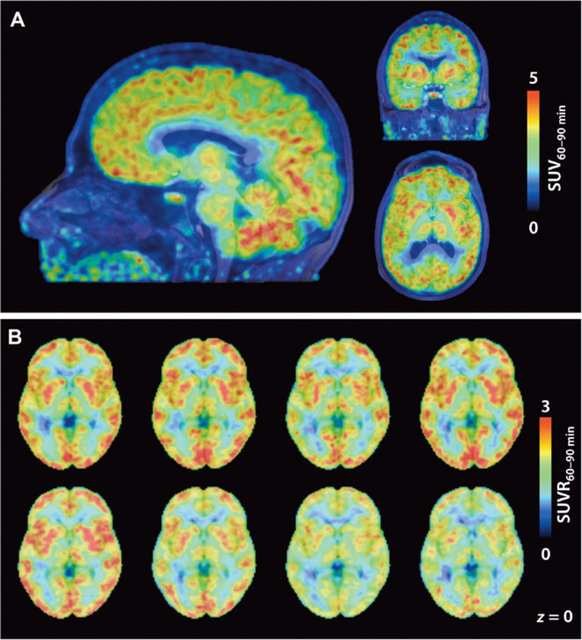

پس از اتصال این ترکیب به " HDACs" دانشمندان توانستند فعالیت مولکولها را با استفاده از اسکن PET در مغز افراد مشاهده و پیگیری کنند. این کار به محققان نشان میدهد که این مولکولها در کدام قسمت از مغز هستند.

نتایج این آزمایشات نشان دادند که سطوح "HDAC" در مخچه که کنترل عملکرد حرکتی را بر عهده دارد بالا بوده و در ماده سفید بسیار پایینتر است. اما هنوز هم اولین گام این نسخه از Martinostat"" تنها با سه نوع از یازده نوع HDAC"" متصل شده و فعالیت هشت نوع دیگر هنوز نامشخص است.